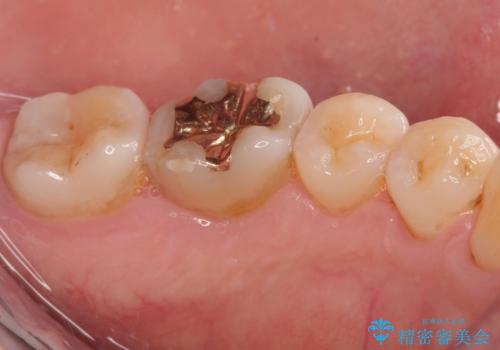

精密検査を行ったところ、上顎左側第二小臼歯のインレー(詰め物)が欠け、その内部に虫歯が進行している状態でした。幸いにも虫歯は神経まで達しておらず、神経を残した治療が可能と判断しました。

まず、虫歯を丁寧に除去。

欠損範囲が大きかったため、オールセラミッククラウンによる補綴治療を行いました。